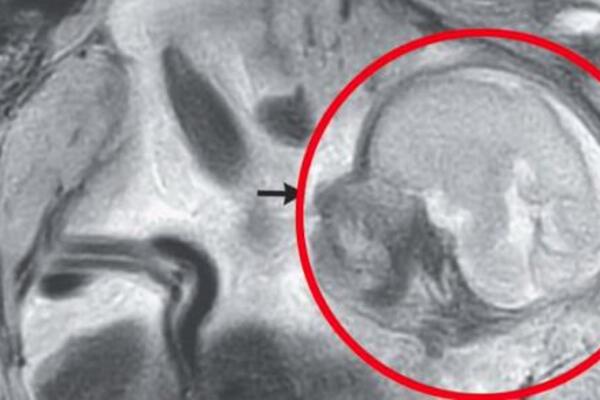

TRIDESETSEDMOGODIŠNJA ŽENA IMALA BOLOVE PA OTIŠLA NA ULTRAZVUK: Kad su lekari videli šta NOSI U SEBI zanemeli su